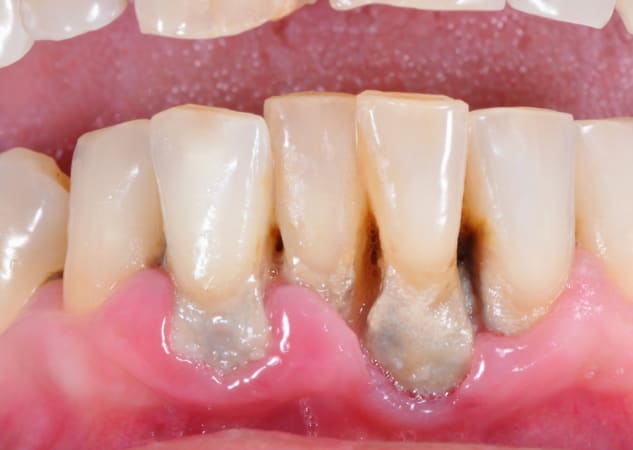

Para que puedas identificarlo visualmente, te ponemos algunas fotos de casos de gingivitis y periodontitis:

Periodontitis